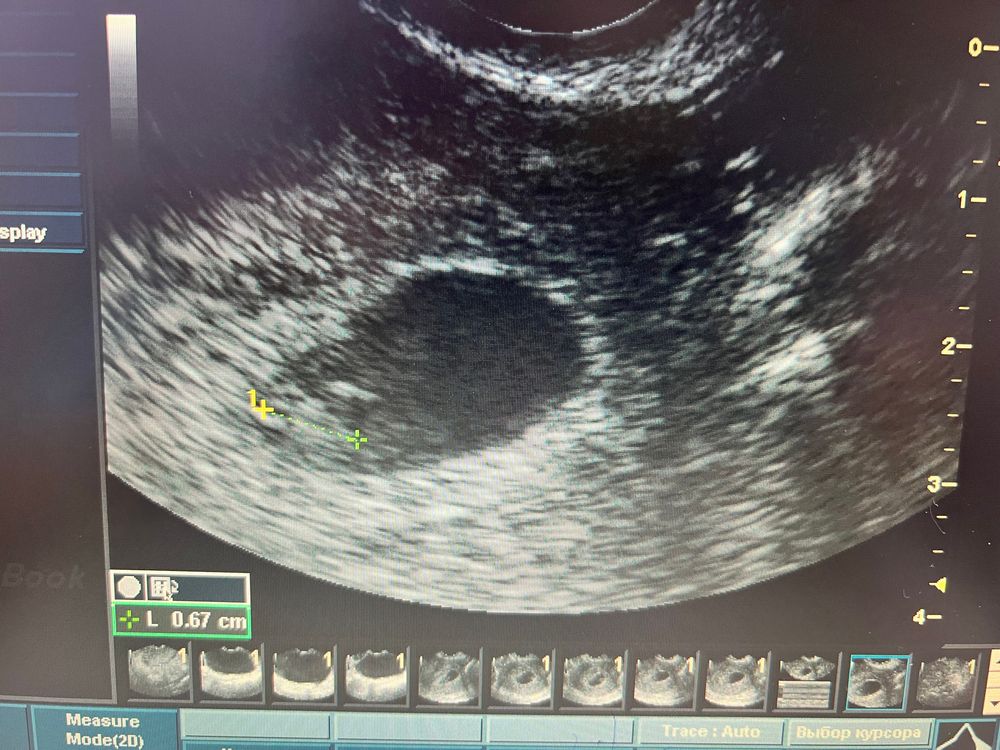

Узи 7 нед 1 день

Беременность- 1 триместр ( только до 10 недель)Сегодня 7 недель 1 день. Была на узи)) уже видно эмбриончик и сердцебиение))) ктр 6.7мм, сб 128, пя 19.8

срок по узи 6 Нед 4 дня)) ну и на первом узи было также )) ну и ладно)

прикрепился он у меня по задней стенке, прячется )))